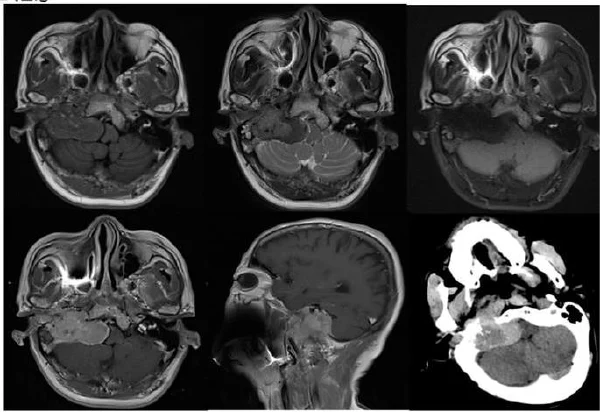

诊断桥小脑角区病变需要结合临床信息、辅助检查结果及医生经验。常用的影像学检查包括磁共振成像(MRI)和计算机断层扫描(CT),这些检查可以帮助明确病变的性质、大小和位置。

由于桥小脑角区的病变可能涉及多个不同的神经结构,全面的神经系统检查也是必须的。医生通常会进行听力测试、眼部检查以评估病变对于颅神经的影响程度。